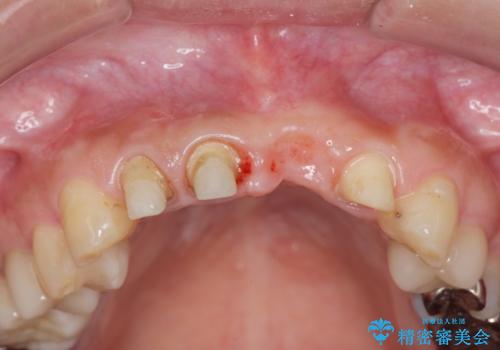

感染したインプラントについて

感染したインプラントからは排膿が間欠的に認められ、掻爬・除去が検討されうるような状況でした。

より審美的な改善を強く求められたため、インプラントを除去し可及的に欠損部顎堤を増大したのちブリッジによる審美改善を行いました。